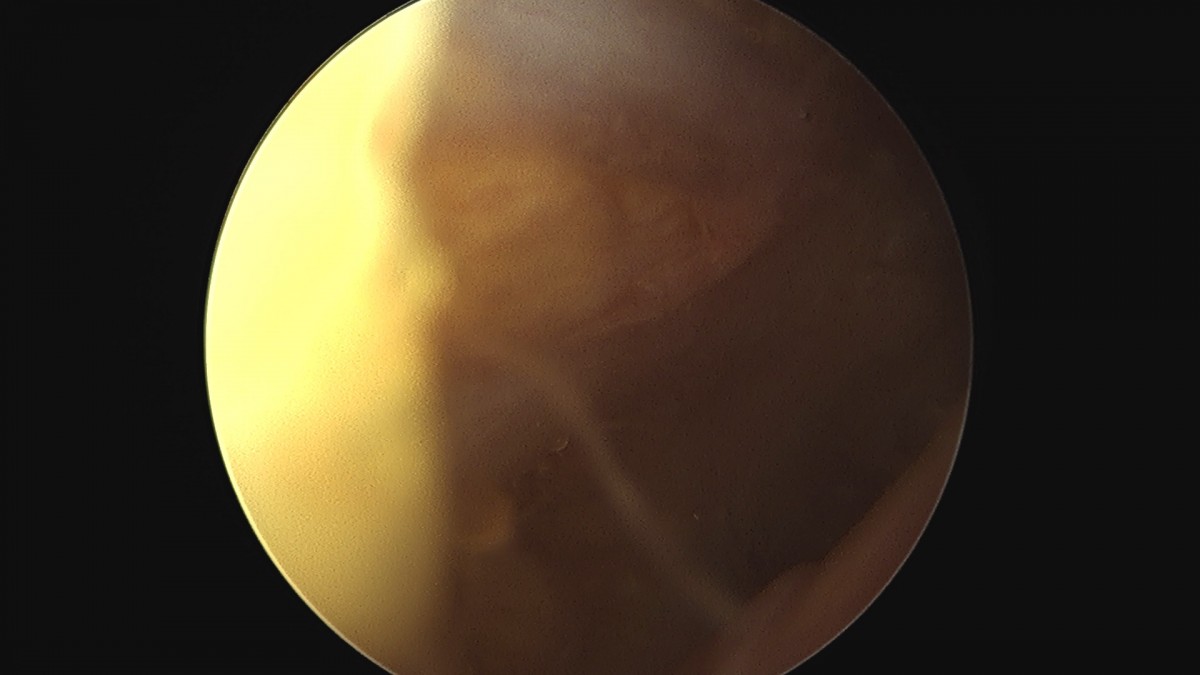

이재상원장님 무릎 반월상 연골판 절제술 안경O 환자

작성자 최고관리자 댓글 0건 조회 374회 작성일 25-09-16 15:58